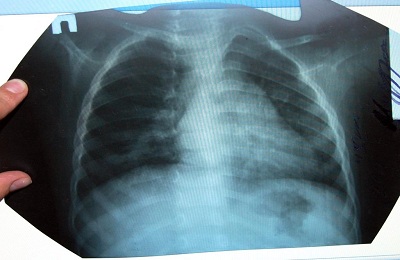

Рентгенологические признаки и лабораторная диагностика воспаления легких

Основным диагностическим методом для постановки диагноза является рентгенография органов грудной клетки. В начальной стадии воспаления легких на рентгенограмме выявляется усиленный легочной рисунок и очаг(и) в виде участка(ов) с пониженной прозрачностью.

В стадии уплотнения на рентгенограмме определяются участки выраженного затемнения, которые окружены воспалительной зоной. В стадии разрешения размеры и выраженность затемнений на рентгенограмме уменьшаются, рисунок ткани легких частично восстанавливается.